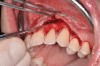

The authors have introduced a laser-assisted vestibuloplasty approach (LAVA) procedure that is designed to prevent recurrent recession after surgical correction, which has been reported in the literature.29,38 This first involves a flap procedure for insertion of the dermal matrix graft material to be used to achieve root coverage and increase zones of existing attached keratinized tissues. To complete the vestibuloplasty procedure, the surgeon separates the mucosal tissues apical to the preexisting mucogingival junction in the area of the teeth exhibiting gingival recession. The authors advocate using a Nd:Yag laser with a power setting at 5 watts to accomplish the vestibuloplasty and release any excessive muscle attachments or frenal pulls in the affected areas (Figure 3).

Fig 7. Laser-assisted split-thickness vestibuloplasty performed.

Figure 7